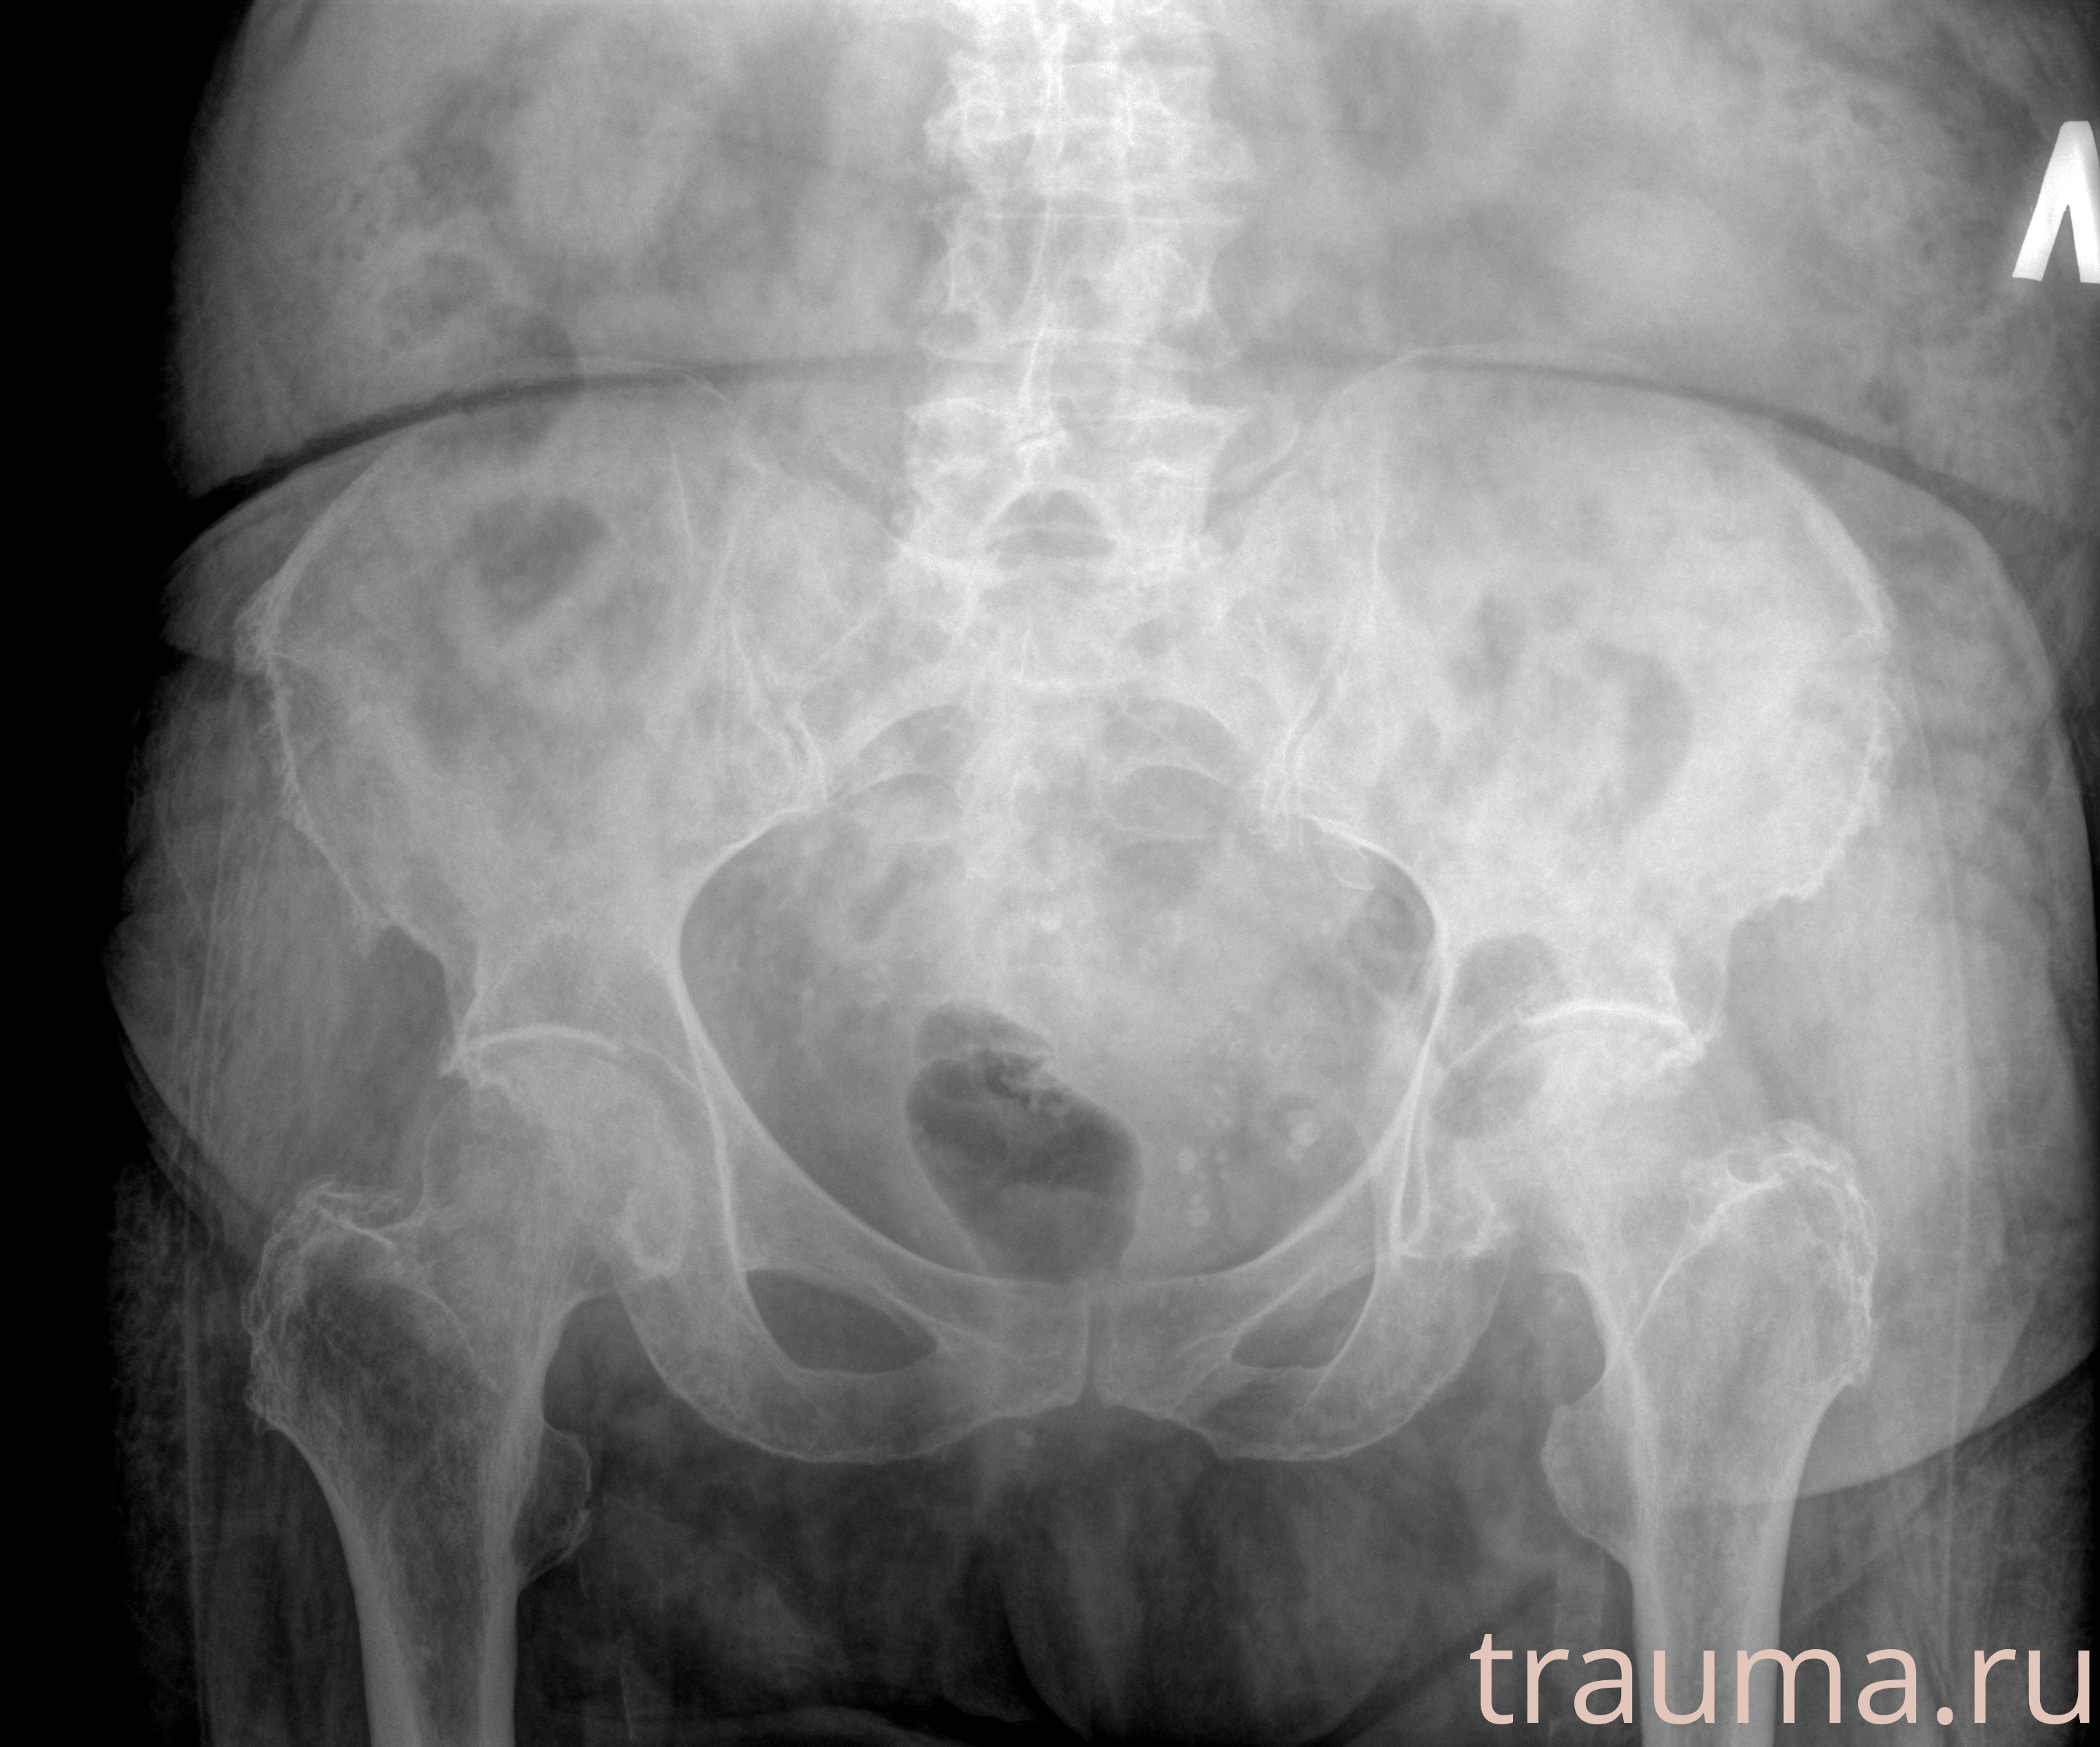

Рентген на дому: по вашему адресу приезжает врач-рентгенолог, травматолог-ортопед с мобильным рентгеновским аппаратом, проводит диагностику травмы или заболевания, делает необходимые рентгенограммы, дает рекомендации по дальнейшему лечению. Получить качественные снимки в домашних условиях возможно благодаря уникальной методике, разработанной МосРентген Центром для института  Склифосовского